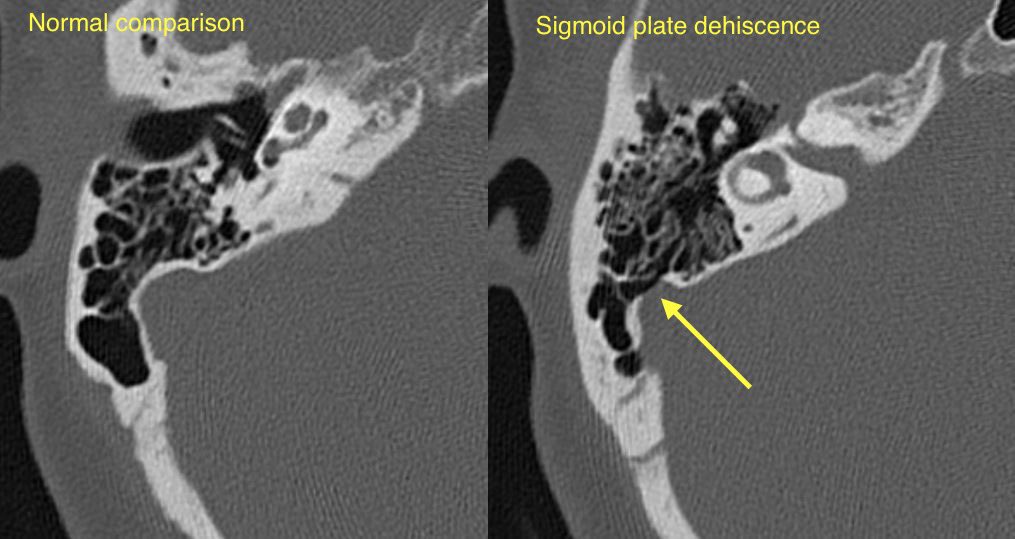

🔷SIGMOID SINUS WALL ANOMALIES

1️⃣Sigmoid plate dehiscence

🔹Sigmoid plate dehiscence: Thinning or absence of the normal cortical bone covering the sigmoid sinus resulting in direct contact of the venous sinus wall with mastoid air cells

💡 Sigmoid plate dehiscence w/ or w/o diverticulum is one of the most common imaging abnormalities at CT for pulsatile tinnitus (up to 40%). These findings are more prevalent in patients with TSS and IIH